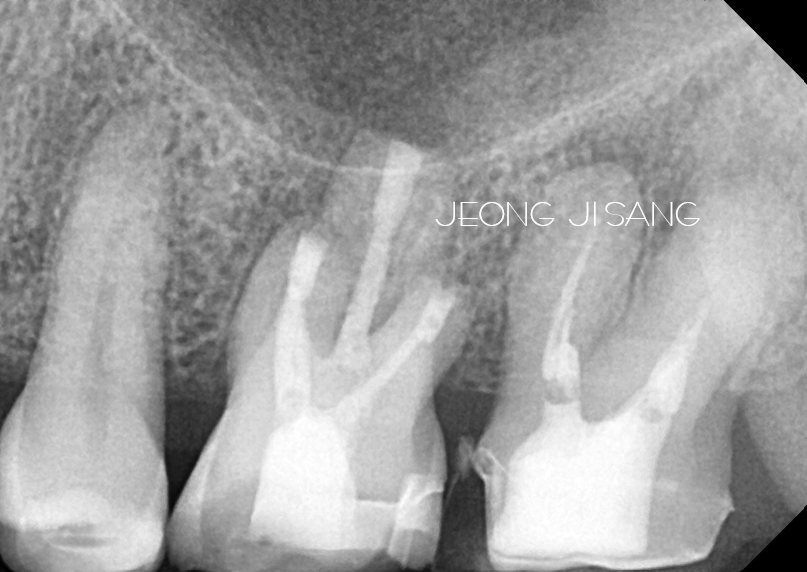

치아 뿌리쪽에 염증이 생겨서 재식술을 통해 치료한 케이스입니다. 좌측 아래 맨 안 쪽 타치과에서 치료받은 치아에 문제가 생겨서 내원하신 분입니다. 어딜가도 발치를…

치아 뿌리쪽 구조때문에 재신경치료가 어려운 케이스로 치아재식술을 통해 치료를 진행했습니다. 보통 신경치료나 재신경치료로 해결이 되지 않는 경우 외과적인 방법으로 치료를 고려해야 합니다.…

치아재식술의 경우 신경치료가 불가능하거나 재신경치료로도 해결이 되지 않을 때 시도해볼 수 있는 치료방법입니다. 또한 외과적인 신경치료방법인 치근단절제술의 적용이 어려운 큰 어금니의 경우에도…